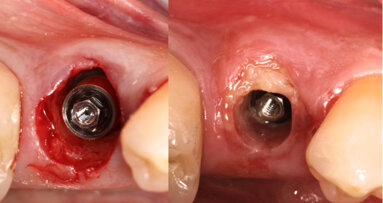

In your webinar, you will also speak about implant stability quotient (ISQ) measurement and resonance frequency analysis by Osstell. How can these tools support dental professionals in the decision-making process? Surprisingly, we still consider ISQ measurement as a new tool! It is such an old concept and has been well studied and validated for many years and documented in numerous articles. It is an indispensable method of objectively evaluating the primary stability of the implant, the most important parameter of success. It helps the dentist to make the right decisions about surgical procedures and the timing of postoperative procedures. In addition, it is very useful in explaining to the patient what we do and why. Despite the fact that we do have this great tool, and the fact that many clinicians propose immediate post-extraction implants or immediate loading, these systems are still available in too few practices.